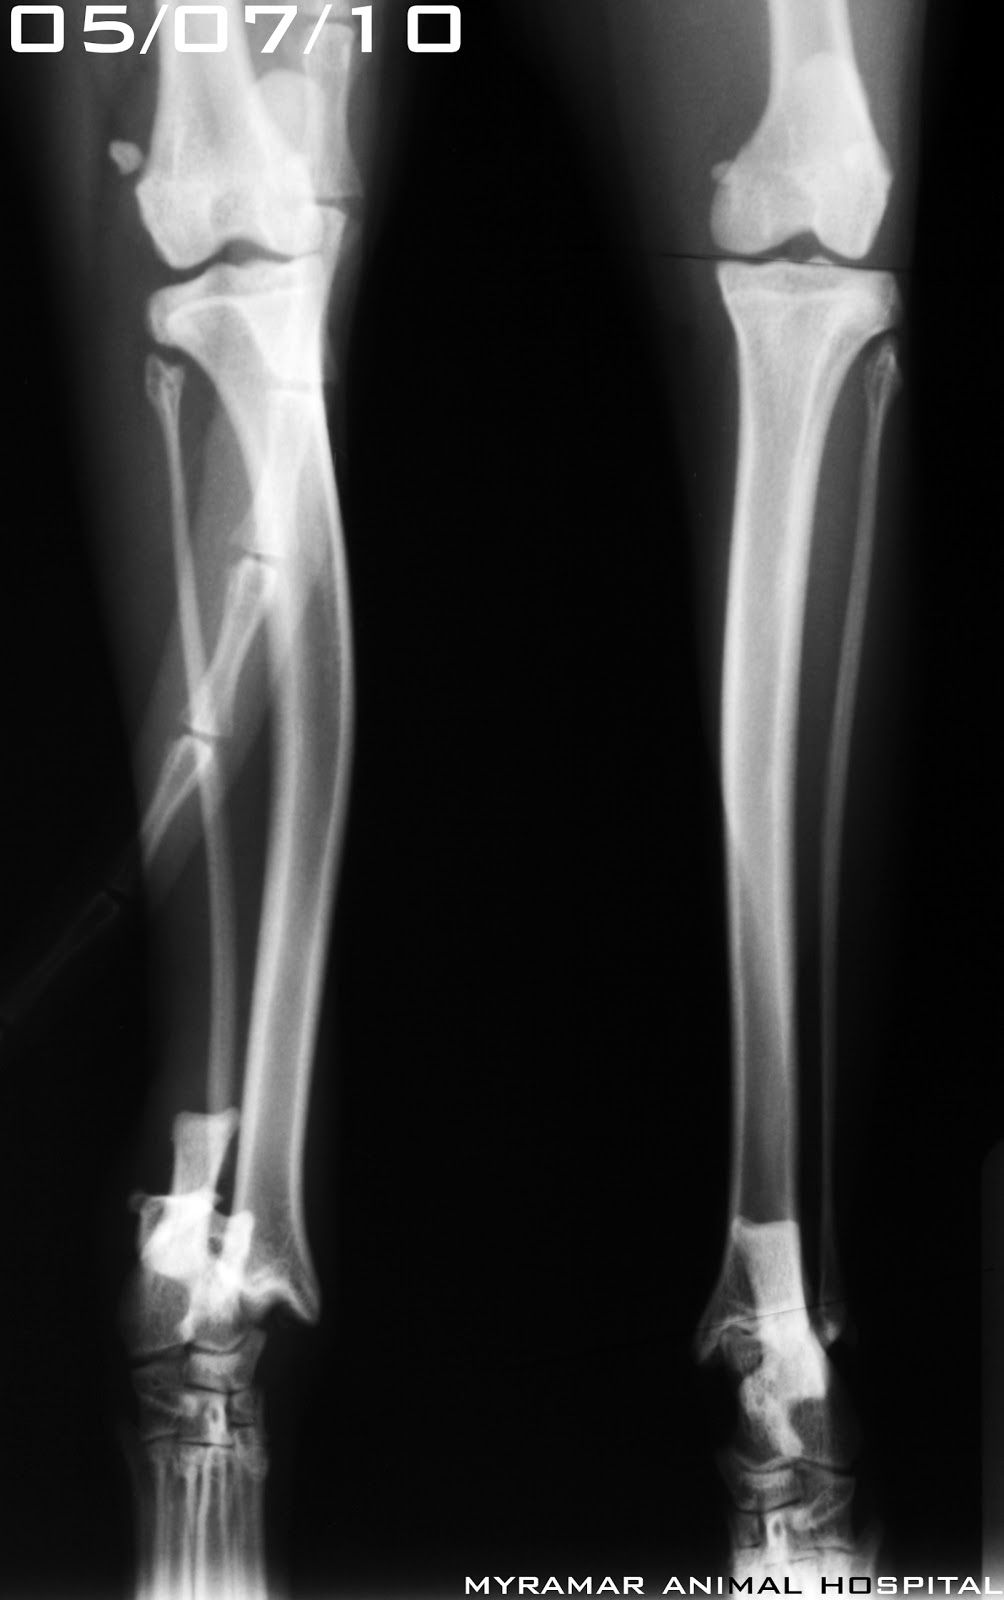

Fractura Maleolo Peroneo Sin Desplazamiento, MALÉOLO PERONEO | Qué es, significado, ubicación, función y lesiones, 4.03 MB, 02:56, 12,945, FisioOnline, 2020-12-15T19:13:43.000000Z, 3, Do You Need an Ankle X-Ray? - Therapydia Portland, therapydiaportland.com, 2000 x 905, jpeg, WebLa fractura del tobillo es una lesión relativamente frecuente. Se caracteriza por la ruptura de la prominencia ósea en la parte externa (tercio distal del. WebFractura no desplazada maléolo peroneo D Mi hija el día 03-03-12 se fracturo el maléolo peroneo sin desplazamiento y el han puesto una férula suropédica. Le estamos., 20, fractura-maleolo-peroneo-sin-desplazamiento, Novedades y Muebles WebLa fractura del tobillo es una lesión relativamente frecuente. Se caracteriza por la ruptura de la prominencia ósea en la parte externa (tercio distal del. WebFractura no desplazada maléolo peroneo D Mi hija el día 03-03-12 se fracturo el maléolo peroneo sin desplazamiento y el han puesto una férula suropédica. Le estamos.

WebAnatomía interactiva. El tobillo está conformado por diferentes zonas anatómicas esenciales para que podamos caminar y desplazarnos. Existen dos zonas prominentes en el tobillo. WebLa fractura puede desplazarse, si es el caso, debe corregirse quirúrgicamente. Pseudoartrosis, esto significa que aún no existe una conexión ósea estable entre los. WebLas fracturas de tobillo se producen en el maléolo medial o posterior de la tibia y/o el maléolo lateral del peroné. Estas fracturas pueden ser estables o inestables.. WebUna fractura se puede clasificar según la ubicación de los fragmentos óseos en: Compuesto: tras la fractura, los fragmentos óseos no sufren desplazamientos con. WebEn esas fracturas se recomienda no cargar la pierna 4-6 semanas. Aunque el mayor riesgo de desplazamiento se produce en las 3 primeras semanas, es posible que se haya. WebEl tiempo de recuperación de una fractura de maleolo peroneal sin desplazamiento suele ser de entre 6 a 12 semanas. ¿Cuánto tarda en curar una fractura de maleolo externo? A. WebFractura del maléolo externo del peroné sin desplazamiento apoyar pie. El 15/11/2013 hace hoy 16 días me fracturé el maléolo externo del peroné sin deplazamiento. Me.

WebMe hice una fractura del perone por el meleolo sin desplazamiento. En principio y en verdad es donde mas descanse, estuve 5 dias hospitalizada con hielo etc.. WebDe hecho, aunque tuvieras la movilidad completa del tobillo y la fuerza de los diferentes grupos musculares de la región fuera competente (normalmente tras 6. WebLa lesión sindesmal en el seno de una fractura de tobillo plantea un reto tanto en el diagnóstico como en la toma de decisiones en cuanto a la necesidad de reducción y el.